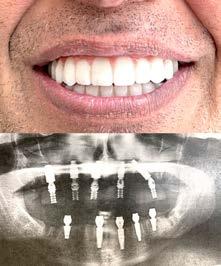

# 1 (2023) • 8 января Газета «Диаспора» – все о нас с вами Questrial Open Sans ПО ВОПРОСАМ РАЗМЕЩЕНИЯ РЕКЛАМЫ ОБРАЩАЙТЕСЬ ПО ТЕЛЕФОНУ: (916) 487-9701 или (916) 705-0739 10 Замещение всех зубов на 4-х, 6-ти имплантах Одиночные импланты Несколько имплантов ИМПЛАНТАЦИЯ ЗУБОВ Установка одного импланта от FREE Consultation and CT-Scan Лучшее качество услуг и материалов по разумной цене! Консультация и 3D снимок в подарок. 911 Reserve Dr., Ste #150, Roseville, CA 95678 | Phone: (916) 827-3605 $998* (916) 827-3605 Высококлассные услуги по Зубной Имплантации в современной клинике, лимиторованной на установку имплантов. * - установка 1 (одного) импланта не включая абатмент и коронку. Имплантация будет производится одним из специалистов клиники под руководством доктора Александра Антипова, челюстно-лицевого хирурга. Цена указана для пациентов, оплачивающих наличными. Все-на-5-ти имплантах + несъемные зубы за 1 день Одна из недавних операций: 5 СОВЕТОВ ДЛЯ ЗДОРОВОГО ПРАЗДНИЧНОГО СЕЗОНА Обезопасьте себя от КОВИД-19 во время праздников. Устанавливать правила - это нормально! Неважно, идет ли речь о том, чтобы все были привиты в срок от КОВИД-19 или сделали тесты, все